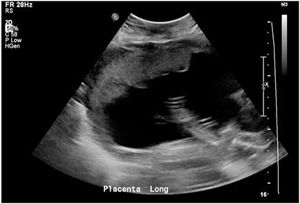

Case History: Pregnant female, 21 weeks 3 days gestational age, G2P1, experiencing severe peri-umbilical pain and a palpable bump just to the right of the umbilicus.